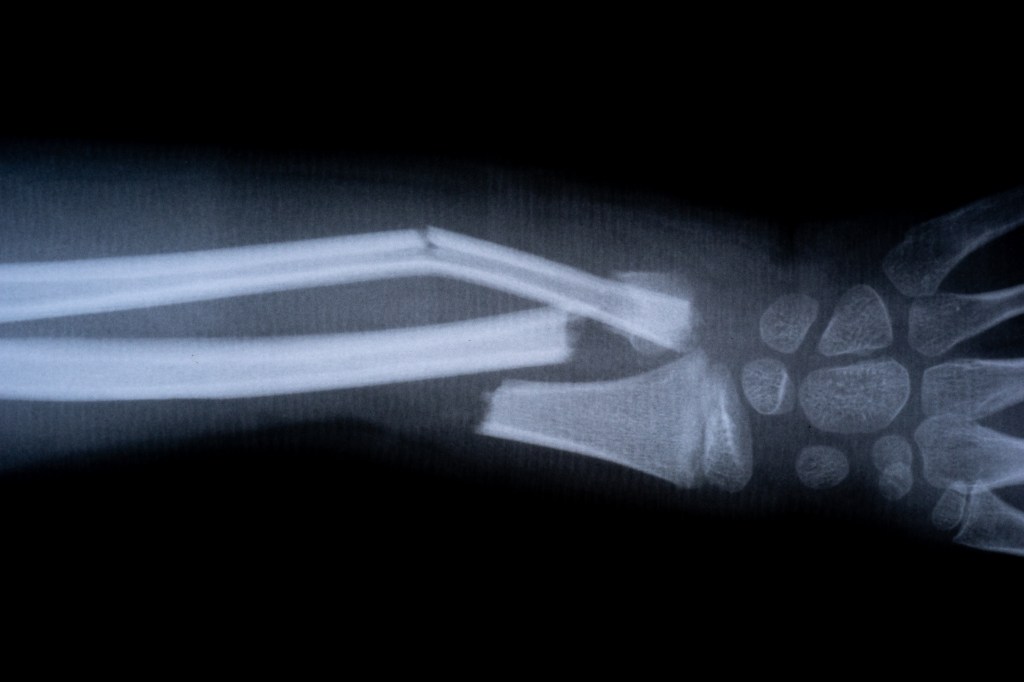

Chinese Scientists Develop ‘Bone Glue’ That Heals Fractures In Minutes